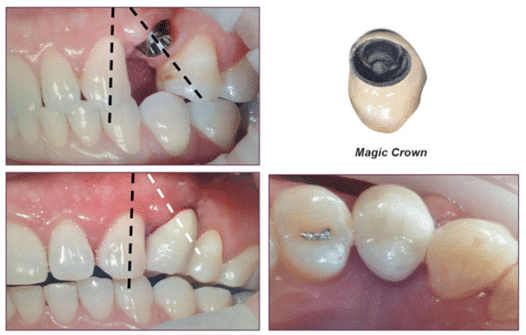

Le Magic Post est conçu avec des connexions externes et internes, offrant un espace de 2 mm pour obtenir l’effet de ferrule à l’extérieur et un espace de 4 mm pour obtenir une connexion interne solide.

Cela permet d’obtenir une double connexion robuste, prévenant le détachement vertical et rotatif de la prothèse. De plus, elle contribue à disperser les forces lors de l’application des forces occlusales, réduisant ainsi considérablement le risque de fracture de l’implant (figure 15).

(Figure 15) Schéma de l’assemblage du Magic Post.

En effet, la hauteur de 2 mm du Magic Post joue un rôle crucial dans l’obtention d’une polyvalence dans la fabrication prothétique. Grâce à sa faible hauteur de 2 mm et à son angle externe incliné, il peut s’adapter à une variété de techniques prothétiques implantaires basées sur la dentisterie implantaire moderne (figures 16, 17).

(Figure 16) Forme spécifique du Magic Post.

(Figure 17) Traitement prothétique implantaire réussi, malgré une faible hauteur osseuse verticale.